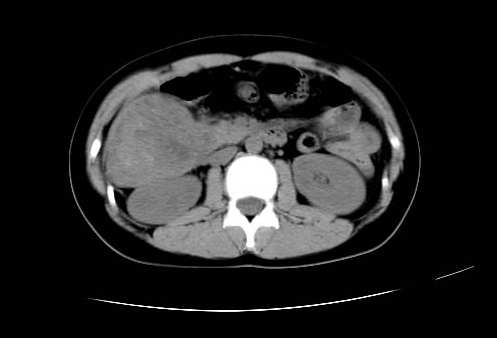

女 16岁  右上腹痛一天,无其他不适

肿块最大径位于十二指肠降段与水平段移行处,并且与肝脏压迹呈“0”形征,可以考虑位于肝外并与胃肠道关系紧密,考虑胃肠道间质瘤(gist)可能较大,须除外神经节起源肿瘤。

肿块与十二指肠关系密切,支持间质瘤诊断.肝脏与结肠均为受压改变.

右下腹巨大肿快,密度不均匀,内见坏死低密度区,边界清楚,与周边胀器明显有分界,未见强化,多考虑来源于间叶组织的良性肿物.

我坚决反对您的观点,该病例定位:横结肠肝曲与升结肠之间的肠系膜及部分肠壁。请看下图:

病灶巨大,少部分向肠腔内生长,大部分向长腔外生长。其密度不均匀,增强显示明显不均匀强化,并见有大片状始终不强化的不规则坏死液化区。虽然病灶中上部形态尚可,病人又如此年轻,但中下部形态、密度、强化特点强烈提示为恶性病灶。综上,我考虑本病例为:恶性胃肠道间质瘤。